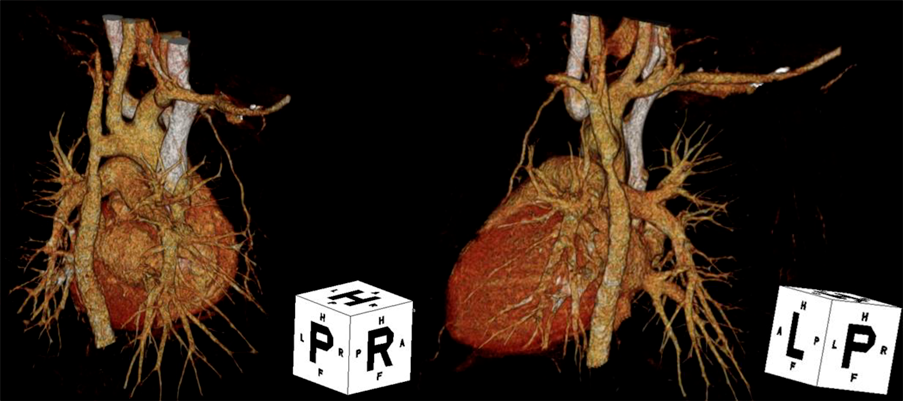

大動脈縮窄術後再狭窄および大動脈弁閉鎖不全症に対して側開胸を併施した正中アプローチによる再手術の1例Combined Full Median Sternotomy with Left Thoracotomy Approach for Recoarctation of the Aorta Associated with Aortic Regurgitation